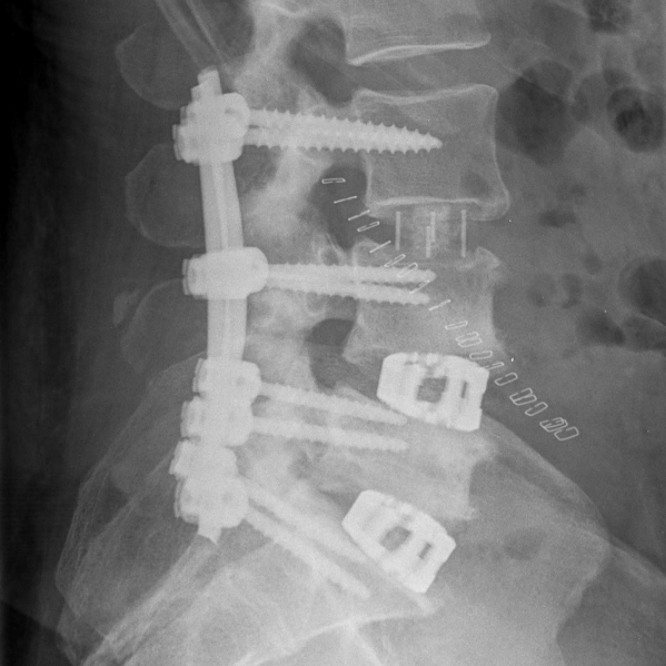

Radiografii din incidenţa anteroposterioară şi laterală ale unui pacient cu spondilolistezis L4-L5 ce a suferit o intervenţie chirurgicală de decompresie şi fuziune intercorporeala posterioară cu şuruburi pediculare şi două cage-uri (TLIF).